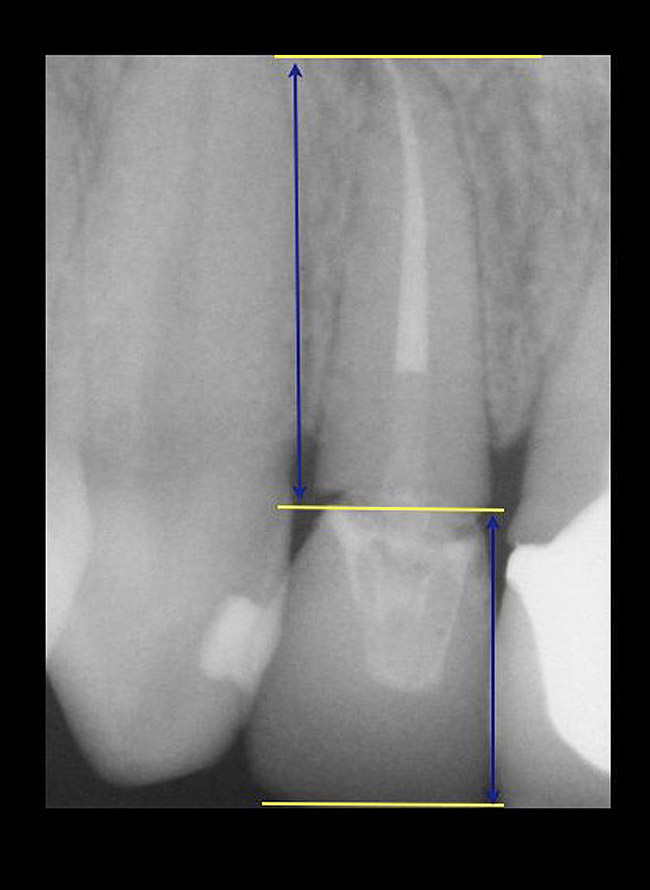

If the tooth has been endodontically treated, the remaining tooth structure relative to the post space needs to be evaluated. The Rule of Thirds is used in this situation. It states that the canal or canal space preparation should not be any wider than one third the mesiodistal root diameter after the endodontic access (Figure 3).3 Once the clinician determines whether adequate tooth structure is present, the second area to evaluate is the distance of the fracture/caries from the crest of bone. To avoid biological width impingement, the minimum distance needed from the osseous crest to the final margin placement is 2.5 mm (Figure 4). As determined in cadaver studies, this consists of approximately 1 mm of connective tissue attachment, 1 mm of junctional epithelium, and 0.5 mm of gingival sulcus.4 This measurement is meant as a guideline and not an absolute number, as it has been shown to have individual variability.5 This actual dimension for the individual patient can be predictably determined by sounding to bone on the adjacent teeth to more closely determine the individual’s biologic width.6

The clinical guideline of 4 mm—consisting of 1.5 mm of tooth structure and 2.5 mm biologic width1,3—is, therefore, the minimum limit for tooth structure above the alveolar bone (Figure 5). If this parameter cannot be met, there are two options for obtaining this threshold. One option is surgical crown lengthening,7,8 and the other is forced orthodontic eruption.9 The choice between each option should be made based on the effect each procedure will have on the esthetics of the case, the crown-to-root ratio, and whether osseous surgery will create a furcation involvement on the adjacent teeth (Figure 6). Esthetic considerations will be addressed later. In terms of crown-to-root ratio, there are two guidelines that exist for determining the minimum ratio (Figure 7). One is the classical 1:1 presented by Penny.10 The second, for maxillary anterior teeth, is 12 mm to 13 mm of tooth with 8 mm to 9 mm of root in bone and 4 mm coronal to the bone, as presented by Spear.1 If all of these criteria for tooth structure are met, then the tooth should be considered an acceptable candidate for retention and restoration. Also, if insufficient tooth structure exists, the required tooth structure can be obtained via forced orthodontic eruption or periodontal surgery provided that the esthetics and periodontal function of the tooth in question and the adjacent dentition are not compromised.